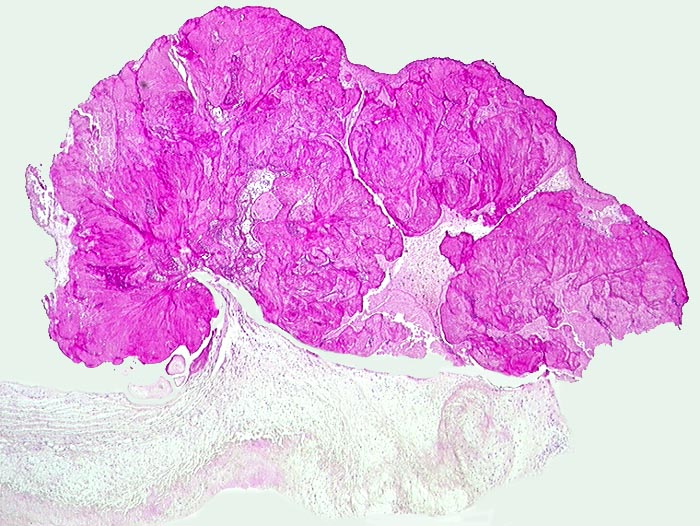

Endocarditis marantica

Aortenklappe

Der Aortenklappe ist eine Vegetation aus Fibrin aufgelagert.

Metastasierendes Bronchuskarzinom.

Histologie